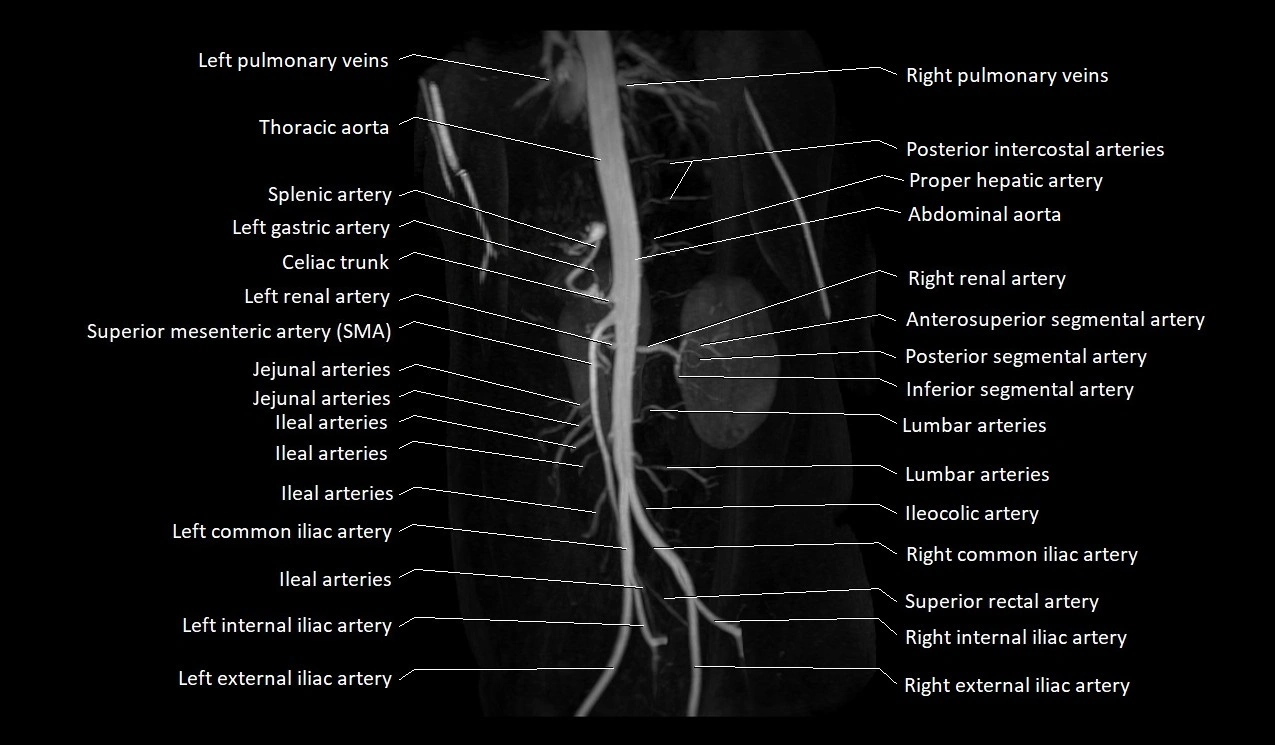

MRA Pelvis with Gadolinium:

-

Clearly delineates the origin, course, and anastomoses of the accessory obturator artery

Identifies connection with inferior epigastric artery, external iliac artery, or obturator artery

Excellent for detecting vascular variants prior to surgery

Useful in mapping pelvic vasculature in trauma, tumor embolization, or preoperative planning